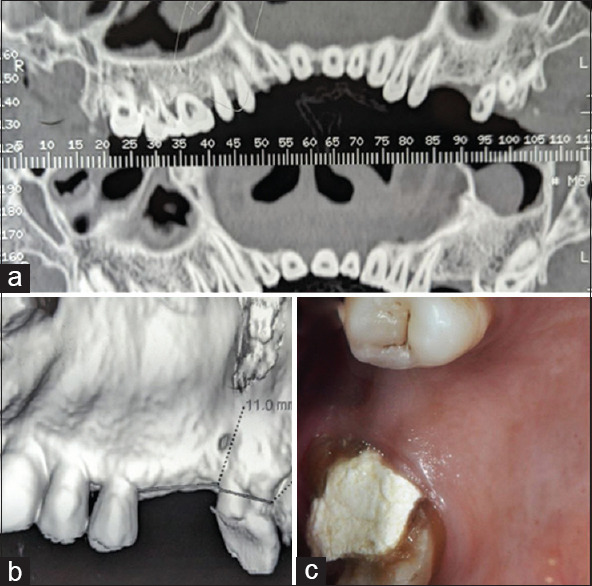

Materials and methods: Thirteen patients were recruited for this split-mouth study, each presenting with a hopeless molar in one quadrant and a partially edentulous ridge with a missing molar in the contralateral quadrant. The compromised molars were atraumatically extracted without flap reflection, followed by immediate placement of ultrawide diameter implants. In the opposing quadrant, missing molar sites were rehabilitated with standard-diameter implants. Crestal bone remodeling, implant stability, and soft-tissue maturation were evaluated 1-year postloading. Radiographic assessments and Osstell device measurements were performed at implant placement, 3 months postrestoration, and 1 year after prosthetic function.

Results: The findings suggest that immediate flapless molar extraction helps preserve vascular integrity, and ultrawide diameter implants may serve as a viable treatment modality for molar replacement. The wider implant surface effectively dissipated occlusal forces, and bone dimensions were well maintained in terms of both width and length. Soft-tissue maturation, including attached gingiva thickness, was favorable after 1 year of prosthetic function. Healed partially edentulous ridges restored with standard-diameter implants also demonstrated stable functional outcomes at the 1-year follow-up. However, a notable limitation of this approach was the inadequate bone volume to accommodate the width of the missing molar crown, leading to occlusal and maintenance challenges. In addition, incomplete papillary fill around implant-supported restorations was observed due to reduced bony dimensions.